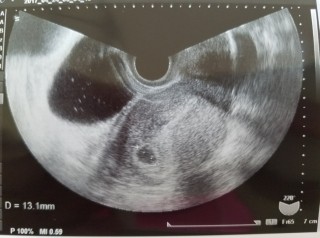

3回の人工授精と2回の体外受精を経て妊娠しました。前回は、化学流産で胎嚢確認できなかったので、胎嚢と卵黄嚢が見れて嬉しいです。大きさは13.3mmでした。